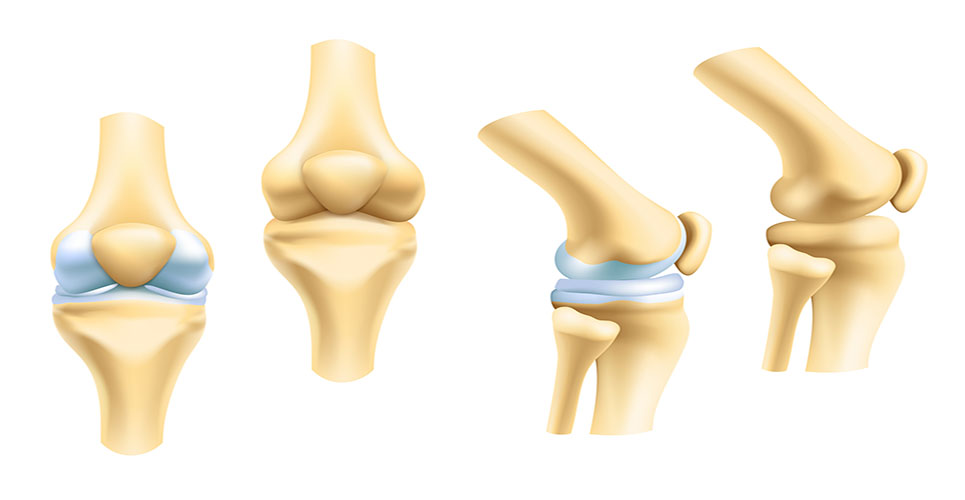

Рисунки Суставов: Анатомические Иллюстрации